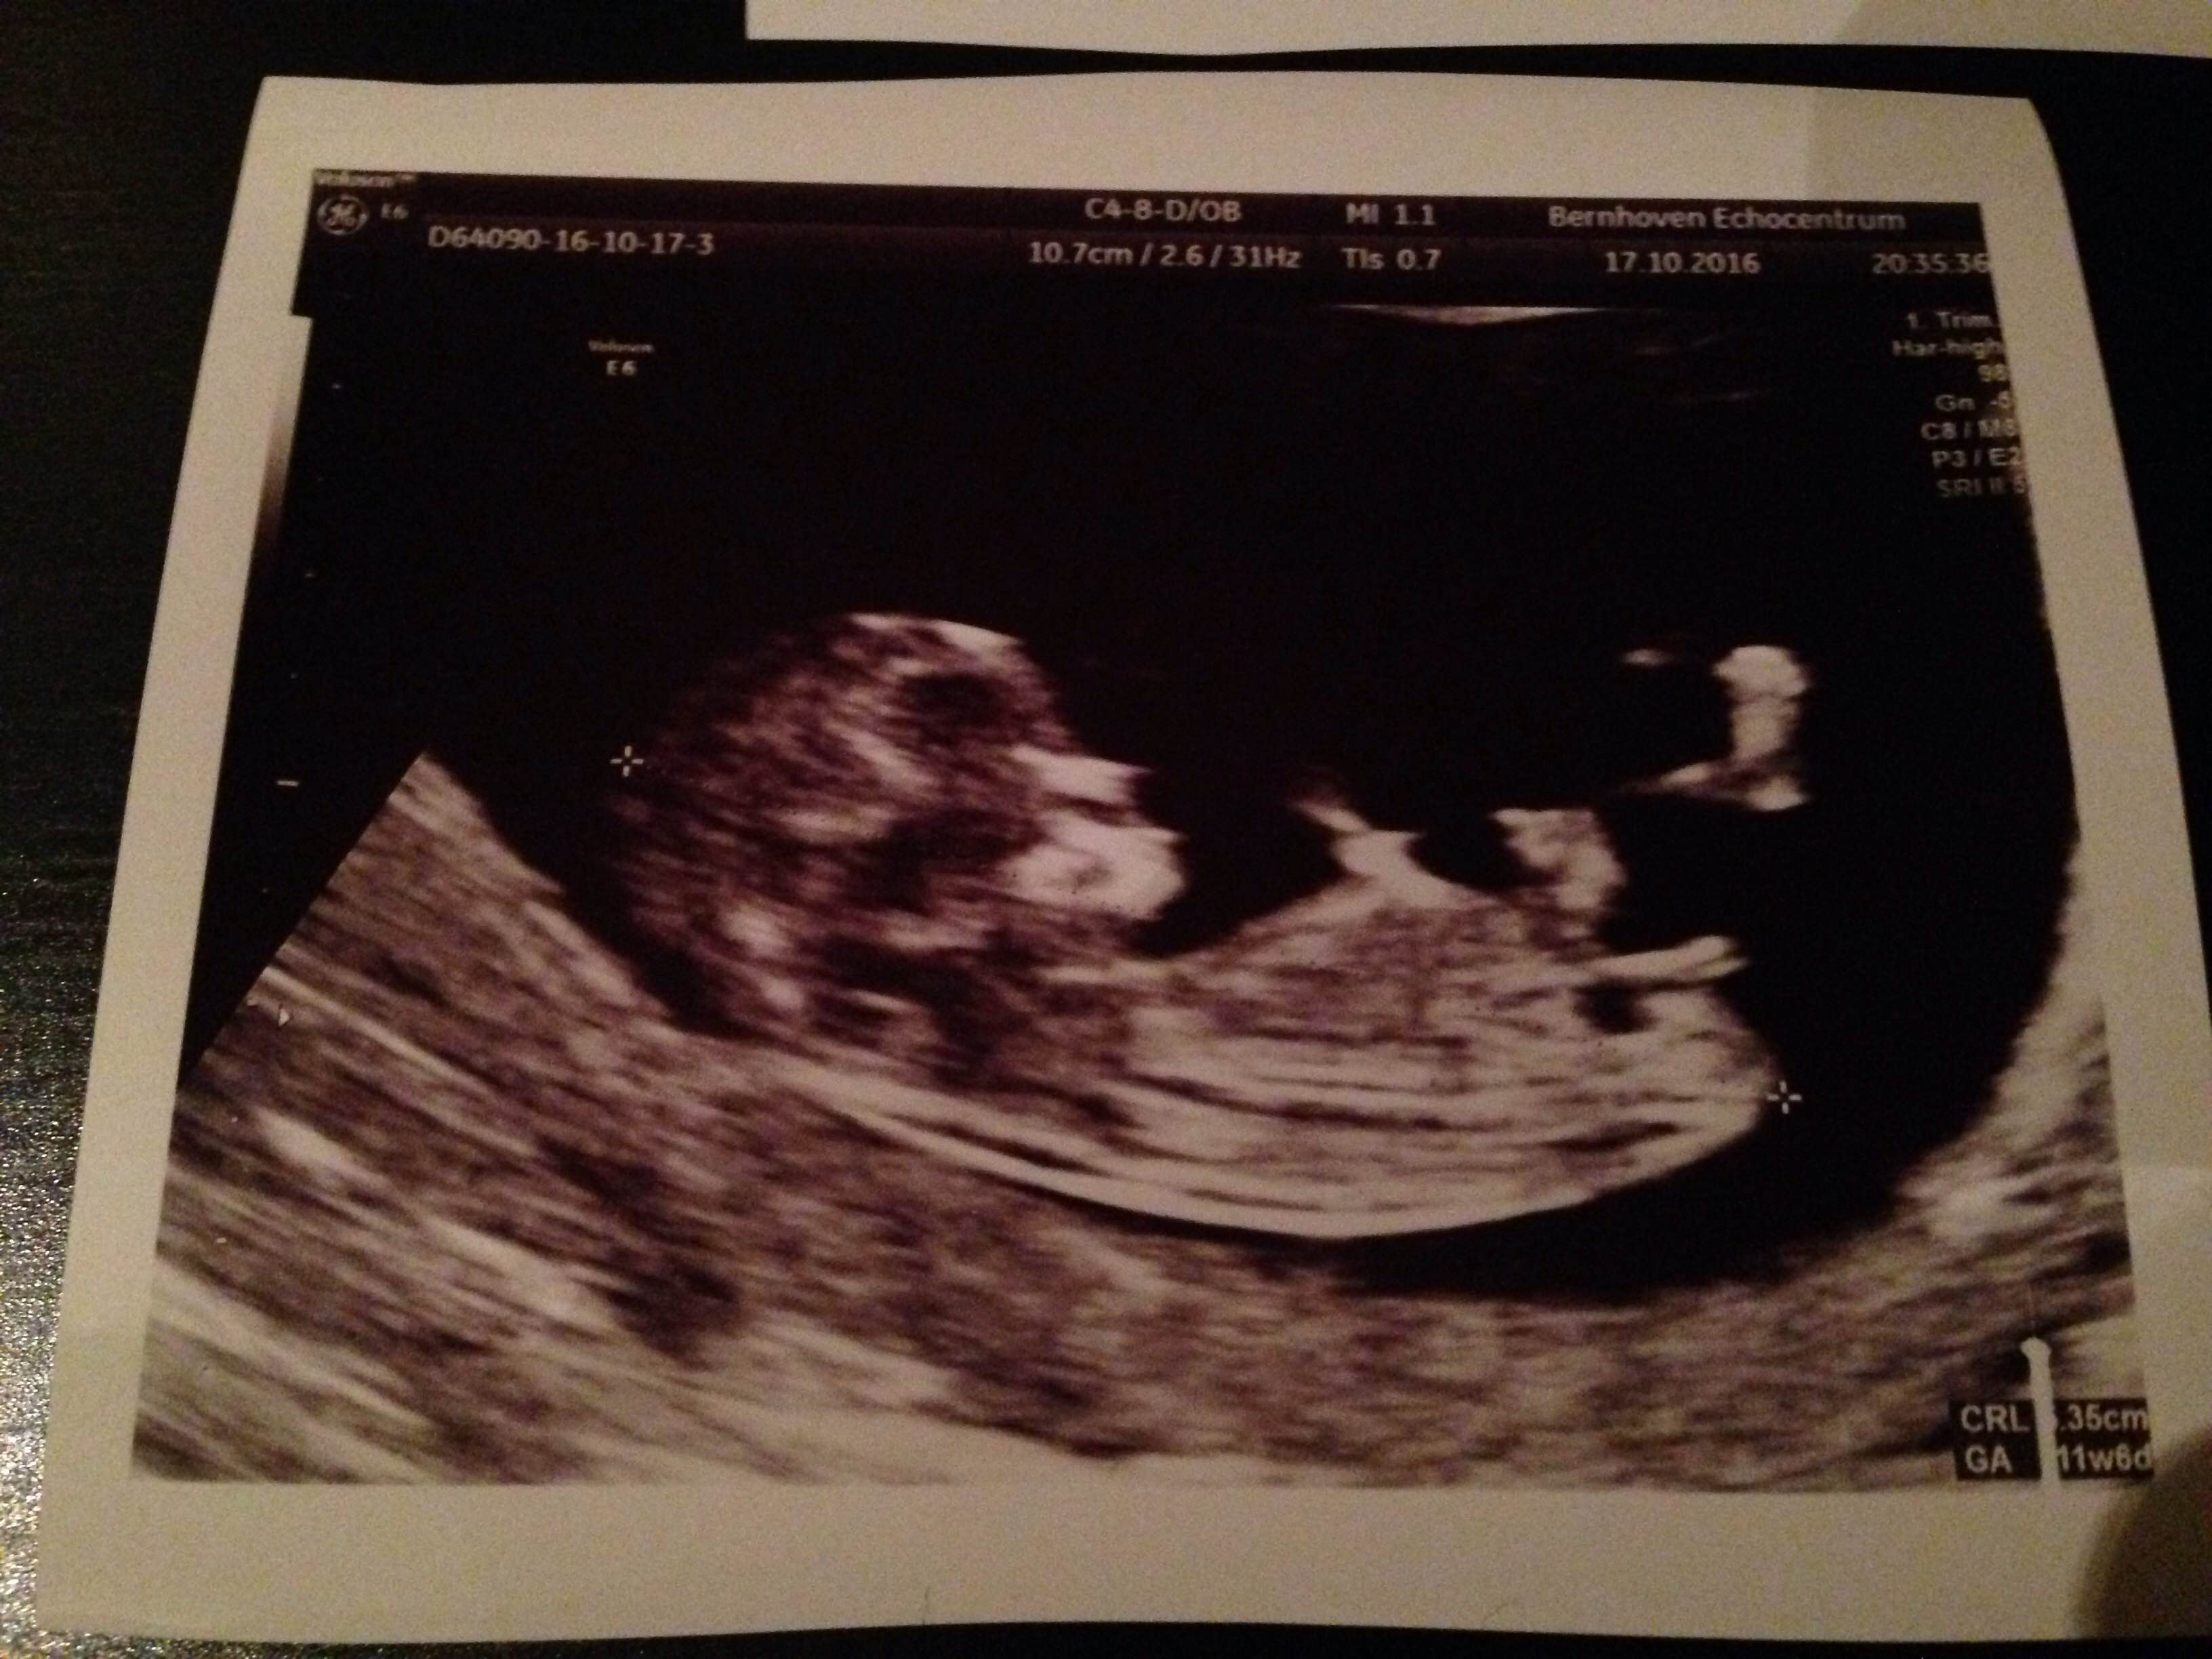

The first two photos are from 11w + 4d, the last one 11w + 6d.

I am so excited to find out, what do you think pink or blue?

Attachment 33456Attachment 33457Attachment 33458